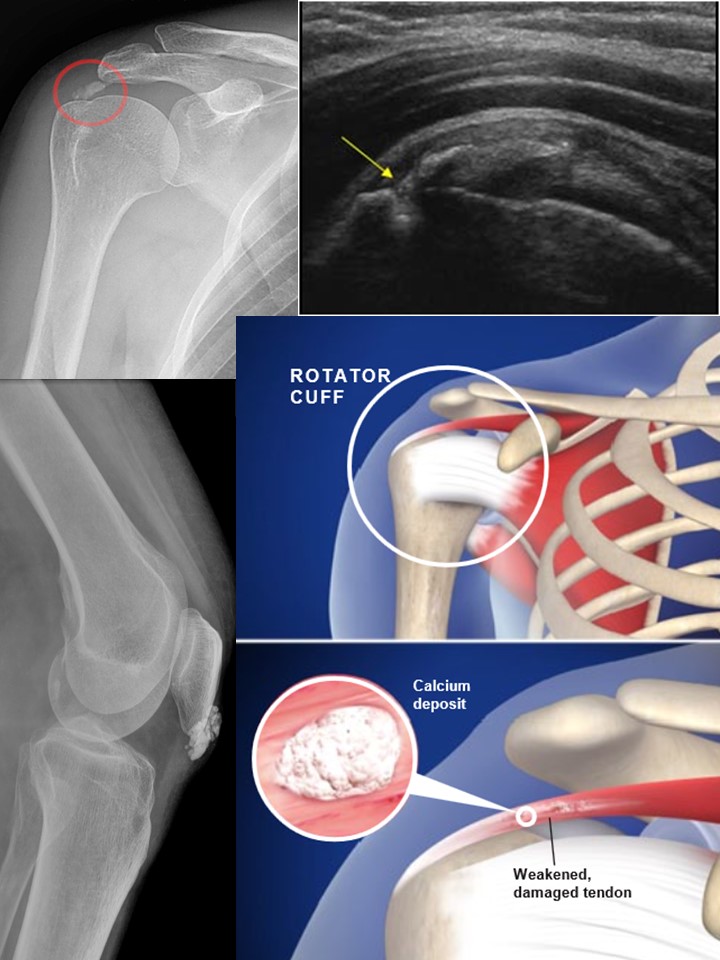

အရွတ်၊အဆစ် အစိတ်အပိုင်းတွေရဲ့ကြားမှာကျောက်တည်ခြင်း Calcification

အဘယ့်ကြောင့် ကျောက်တွေတည်ရသလဲကို ရှင်းပြရပါက အရွတ်၊အဆစ်၊ အရည်အိတ် bursa၊ ကြွက်သား စသည့် အစိတ်အပိုင်းတွေရဲ့ကြား calcium hydroxyapatite လို့ခေါ်သော ထုံးဓါတ်ပစ္စည်းများ အနည်ကျလာရာမှ ဖြစ်လာပါသည်။ ပုခုံးတွင် အဖြစ်များတတ်သော်လည်း ခြေထောက် feet ၊ လက်ဖဝါး hands ၊ တင်ပါးဆုံ hips ၊ လည်ပင်းရိုး cervical spine စသည်တွင်လည်း အခြားအစိတ်အပိုင်းများထက် ဖြစ်ပွားမှုများသည်ဟု သိရပါသည်။ အသက် ၃၀ မှ ၆၀ ကြား ကာလ နှင့် အမျိုးသမီးများမှာ ဖြစ်ပွားမှုပိုများလေ့ရှိပါသည်။ .#ဖြစ်စဉ်အဆင့်ဆင့် ပထမအဆင့် Pre-calcific stage တွင် အရွတ်စသည်တို့ထဲ၌ အရိုးနုပုံစံ ဆဲလ်များ fibrocartilaginous metaplasia အဖြစ် အသွင်ပြောင်းလာပြီး အနည်များစုပုံလာစေရန် ဆွဲဆောင်ပါတော့သည်။ အရွတ်လေးတွေဟာ ကြိမ်ဖန်များစွာ ဖိအား၊ ထိခိုက်မှုတွေက တဆင့် မာသော အသွင်ပြောင်းလာရာမှ စတယ် လို့ယူဆကြပါသည်။ဒုတိယ အဆင့်ကတော့ Crystal formation stage ထုံးကျောက်များ အနည်ကျတဲ့ အဆင့် ဖြစ်ပါသည်။တတိယ အဆင့်ကတော့ ခန္ဓာက ပြသနာကို ဖြေရှင်းဖို့ လုပ်လာတဲ့ Resorption အဆင့် ဖြစ်ပါသည်။ ဤအဆင့်တွင် ရုတ်တရက် ရောင်ရမ်းလာခြင်း၊ အလွန်နာကျင်လာခြင်း ဖြစ်စေတတ်ပါသည်။ ထုံးကျောက်တွေကို ဝါးမြိုရှင်းထုတ်ဖို့ ဆဲလ်တွေထွက်လာရာမှ ရောင်းရမ်းခြင်းတွေစတယ်လို့ ပြောကြသော်လည်း အတိအကျကတော့ မရှင်းမလင်းဖြစ်နေတုန်းပါ

#ရောဂါရှာဖွေခြင်း

ဓါတ်မှန်ရိုက်ကြည့်ခြင်းဖြင့် ငွေကုန်ကြေးကျသိပ်မများပဲ ကျောက်များကို ရှင်းရှင်း မြင်တွေ့နိုင်သည်။ တယ်လီဗွီးရှင်း ဓါတ်မှန်ဖြင့် ငွေကုန်ကြေးကျသိပ်မများ၊ ဘေးထွက်ဆိုးကျိုးကင်းကင်းဖြင့် ကျောက်များကို ဖေါ်ထုတ်နိုင်သည်။ ကျန် ငွေကုန်ကြေးကျများတတ်သော MRI, CT Scan စသည်တို့နှင့်လည်း ဖေါ်ထုတ်နိုင်သည်။